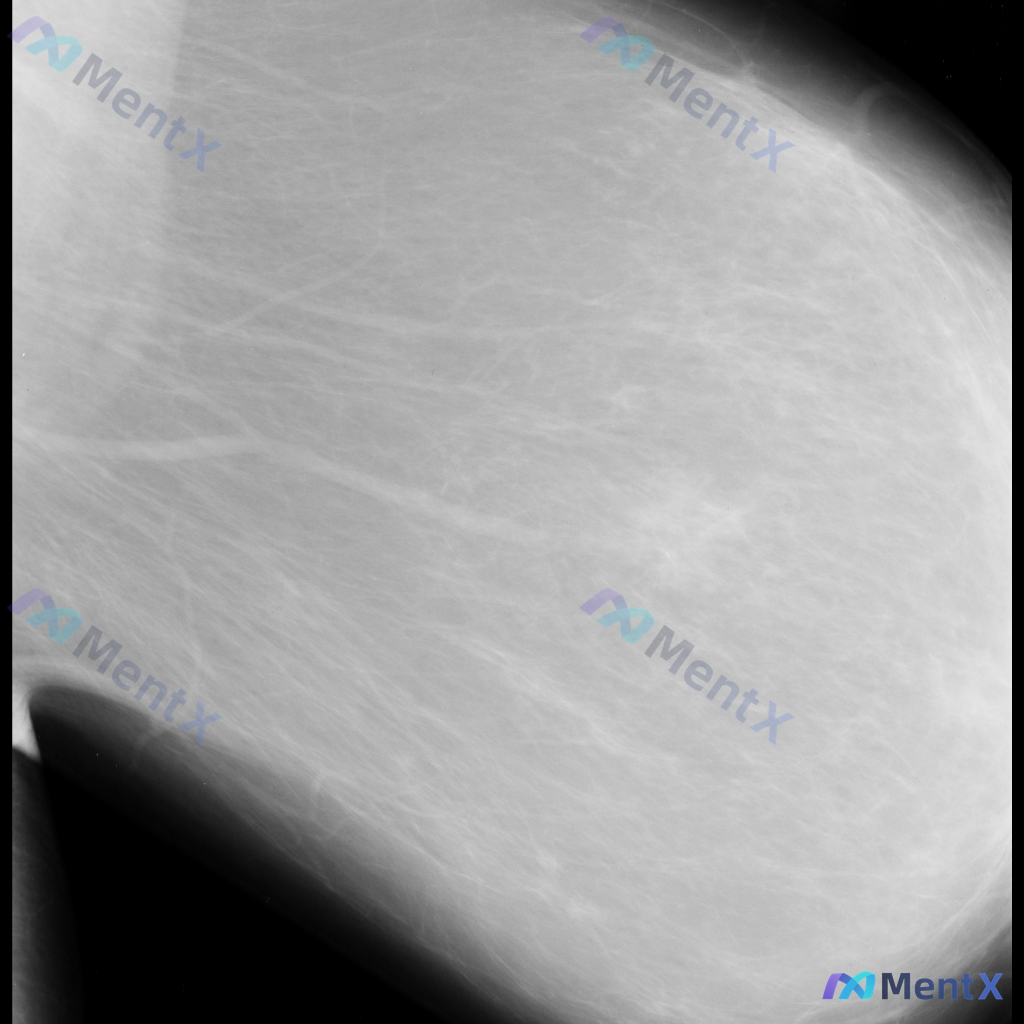

- 图像类型:单张乳腺钼靶侧位片(具体投照体位未明确,无对侧对比)

- 乳腺构成:不均匀致密型(ACR C型),腺体密度较高

目前可见的影像表现

- 图像中部偏外侧的纤维腺体组织结构走行略显紊乱,但不足以诊断为明确的结构扭曲

- 可见模糊的密度稍高影,但缺乏典型肿块的形态和边界特征

- 未见明确的毛刺状肿块,也未见可疑的簇状/线样钙化、星芒状结构扭曲